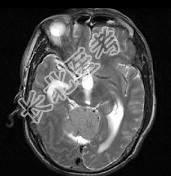

单项选择题男,61岁, 头晕头痛伴行走不稳1月余,请根据所提供图像, 选择最可能的诊断是 ( )

A、淋巴瘤

B、转移瘤

C、胶质瘤

D、髓母细胞瘤

E、(天幕切迹缘)脑膜瘤